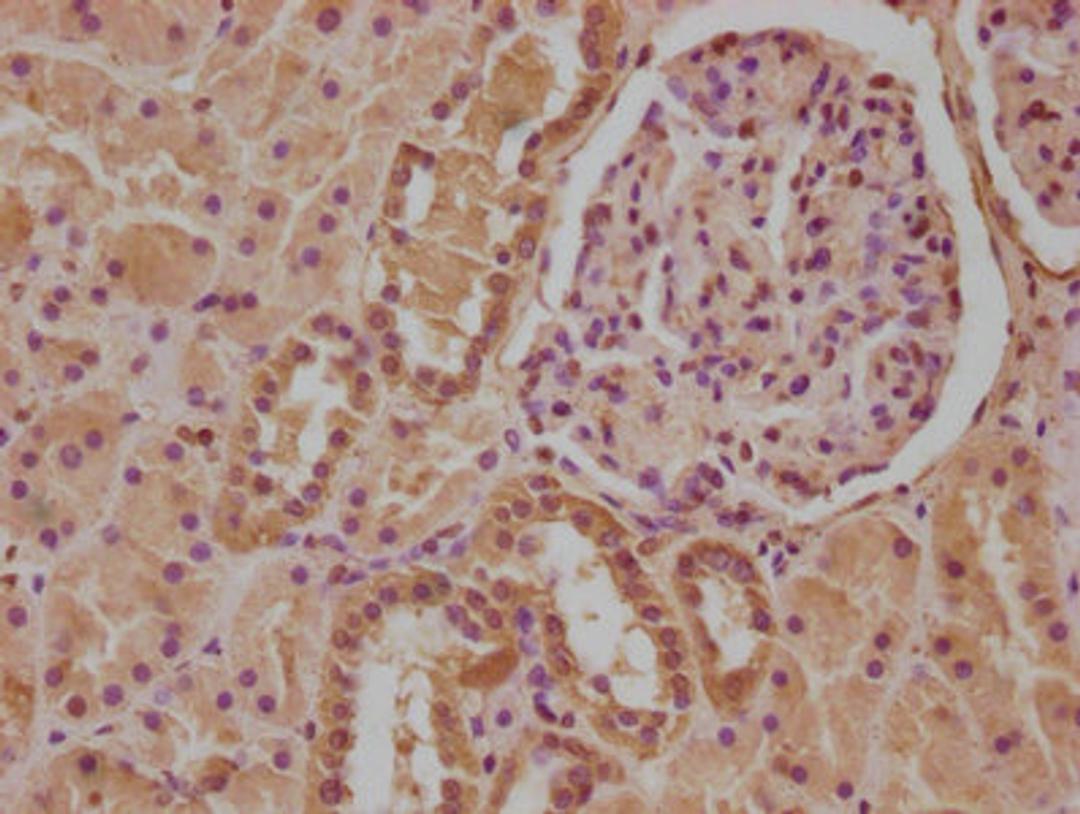

IHC image of CSB-PA011591LA01HU diluted at 1:100 and staining in paraffin-embedded human kidney tissue performed on a Leica BondTM system. After dewaxing and hydration, antigen retrieval was mediated by high pressure in a citrate buffer (pH 6.0). Section was blocked with 10% normal goat serum 30min at RT. Then primary antibody (1% BSA) was incubated at 4°C overnight. The primary is detected by a biotinylated secondary antibody and visualized using an HRP conjugated SP system.